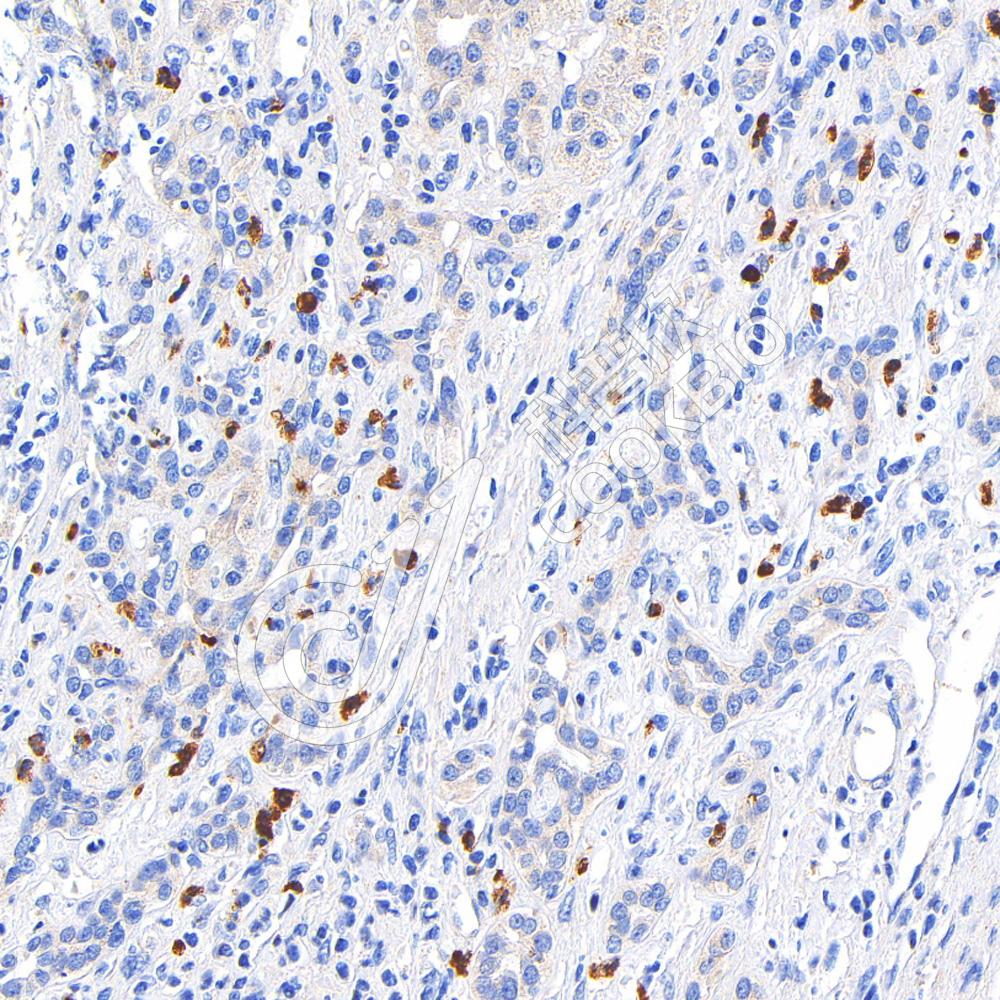

IHC检测CD177蛋白(货号 K1345153).

样品: 人胃癌, 4%多聚甲醛 (货号KSG1101) 固定12-24小时.

抗原修复: 柠檬酸抗原修复液(干粉, pH 6.0) (KSG1201), 98℃, 20分钟.

—抗: 1: 400稀释, 4℃ 孵育过夜.

二抗: S-vision免疫组化多聚二抗(山羊抗兔),即用型 (货号KB3906), 室温孵育20分钟.

样品: 人肝癌, 4%多聚甲醛 (货号KSG1101) 固定12-24小时.